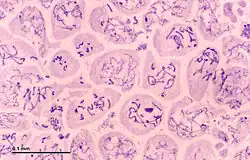

Na puberdade, as espermatogónias localizadas nas paredes dos túbulos seminíferos dos testículos são ativadas e começam a dividir-se por mitose, formando dois tipos de células A que possuem um núcleo oval com um nucléolo ligado ao invólucro nuclear; um dos tipos é escuro ou Ad (escuro) e o outro é claro ou Ap (claro). As células Ad são espermatogónias que permanecem no compartimento basal (região externa do túbulo); estas células são uma reserva de células estaminais espermatogoniais que geralmente não sofrem mitoses. O tipo Ap são células estaminais espermatogónias em divisão ativa, que começam a diferenciar-se em espermatogónias do tipo B, que possuem núcleos arredondados e heterocromatina ligadas ao envelope nuclear e ao centro do nucléolo.[4] As células do tipo B deslocam-se para o compartimento adluminal (em direção à região interna do túbulo) e transformam-se em espermatócitos primários; este processo é concluído em 16 dias.[2][5]

Os espermatócitos primários são células diploides, que no interior do compartimento adluminal continuam a dividir-se, iniciando-se a primeira divisão meiótica na qual se originam duas células-filhas, os espermatócitos secundários haploides (com cromossomas de duas cromátides), processo que dura 24 dias. Cada espermatócito secundário forma duas espermatídeos durante a segunda divisão meiótica. As espermatídeos são também células haploides, mas com cromossomas de cromátide única.[1] Durante as divisões mitótica e meiótica das espermatogónias e dos espermatócitos, a citocinese (divisão do citoplasma) é incompleta e as células estão unidas por pontes citoplasmáticas formando sincícios. As espermatídeos finais são também sincícios e, uma vez que amadurecem em espermatozóides, desprendem-se desses sincícios e passam para o lúmen do túbulo seminífero.